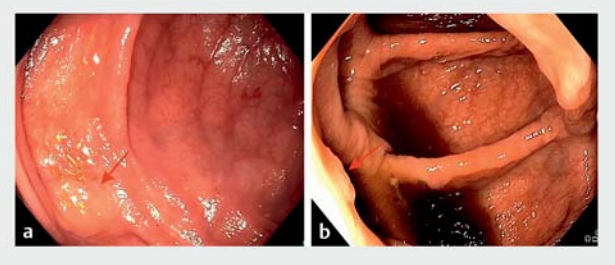

GI Genius第二版未检测到位于右侧结肠10.20秒的Paris 0-IIa型无蒂锯齿状腺瘤(SSA)(图1a)。根据德国和美国指南,这将导致患者随访延迟7年。 Endo-AID(B型)未在右侧结肠中检测到存在0.87秒的巴黎0-IIa息肉(图1b),内镜医师也未看到。

图1. 未检测到的息肉图像:a通过GI Genius版本2;或b通过Endo-AID使用检测类型B。